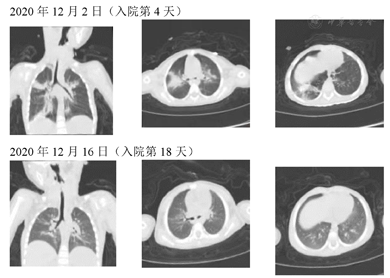

患儿,女性,1岁8个月,因发热、咳嗽、喘息、声音嘶哑4 d入院。患者4 d前无明显诱因出现发热,热峰39.8℃,予口服退热药可降至正常,易反复,4次/d,阵发性犬吠样咳嗽,伴喘息以及声音嘶哑,病初症状较轻,后逐渐加重,无呼吸困,无呕吐、腹泻,无皮疹,无抽搐,无关节肿痛。病初就诊于当地诊所,予口服小儿氨酚黄那敏颗粒、小儿肺喘颗粒、头孢类药物2 d,效差,后住院治疗2 d,予阿糖腺苷、甲泼尼龙琥珀酸钠、氨溴索、阿奇霉素治疗。体格检查:体温39.2℃,脉搏132次/min,呼吸34次/min,神志清,精神反应稍差,咽充血,扁桃体无肿大,口腔内无疱疹,呼吸稍促,三凹征阴性,无鼻翼扇动,无点头呼吸,双肺呼吸粗,可闻及吸气性喉鸣以及喘鸣音。心腹神经系统查体未见阳性体征。辅助检查:入院时血常规:白细胞2.56×109/L,中性粒比例68.7%,CRP正常。PCT 3.68 ng/ml,红细胞沉降率52 mm/h,细菌内毒素:111.15 pg/ml;肝功肾功心肌酶电解质免疫功能均未见异常。入院第4天复查血常规白细胞9.3×109/L,中性粒比例72.3%,CRP 43.75 mg/L。PCT1.2 ng/ml。13项下呼吸道多重细菌核酸检测:肺炎链球菌,耐甲氧西林葡萄球菌。7项呼吸道病原体核酸检测(RNA):阴性。痰培养:耐甲氧西林葡萄球菌。胸部/咽喉部CT以及气道重建提示:1.肺炎;2.气道上段条状异常密度影,右肺上叶支气管管腔狭窄,显示不清,4.咽喉部CT扫描未见异常。心脏、腹部彩超:未见异常。纤维支气管镜检查:声门及声门周围、气管内、右主支气管均可见大量纤维素样坏死物附着。患儿入院后予头孢他啶抗感染、甲泼尼龙琥珀酸钠抗炎3 d后仍有声嘶、呼吸困难、吸气性喉鸣均未见好转,入院第4天行胸部CT及气道重建,怀疑存在急性纤维素性喉气管炎,予行支气管镜检查明确诊断,症状好转,期间病原学明确存在耐甲氧西林葡萄球菌后予万古霉素抗感染,入院第6天再次行支气管镜检查,症状明确缓解;后于第9天、16天行支气管镜检查,镜下声门及声门附近仍可见纤维素样坏死物附着,气管支气管管腔通常,临床症状完全消失。入院第18天复查胸部CT以及气道重建气管狭窄基本消失。随访10个月,患儿未再复发(图1、图2)。